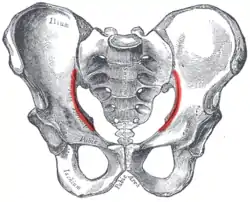

Male pelvis. (Arcuate line shown in red.) | |

The arcuate line of the ilium is a smooth rounded border on the internal surface of the ilium. It is immediately inferior to the iliac fossa and Iliacus muscle.

It forms part of the border of the pelvic inlet.

In combination with the pectineal line, it comprises the iliopectineal line.[1]

The arcuate line marks the border between the body (corpus) and the wing (ala) of the ilium, and, running inferior, anterior, and medial from the auricular surface to the area corresponding to the acetabulum, it also indicates where weight is transferred from the sacroiliac joint to the hip joint.[2]